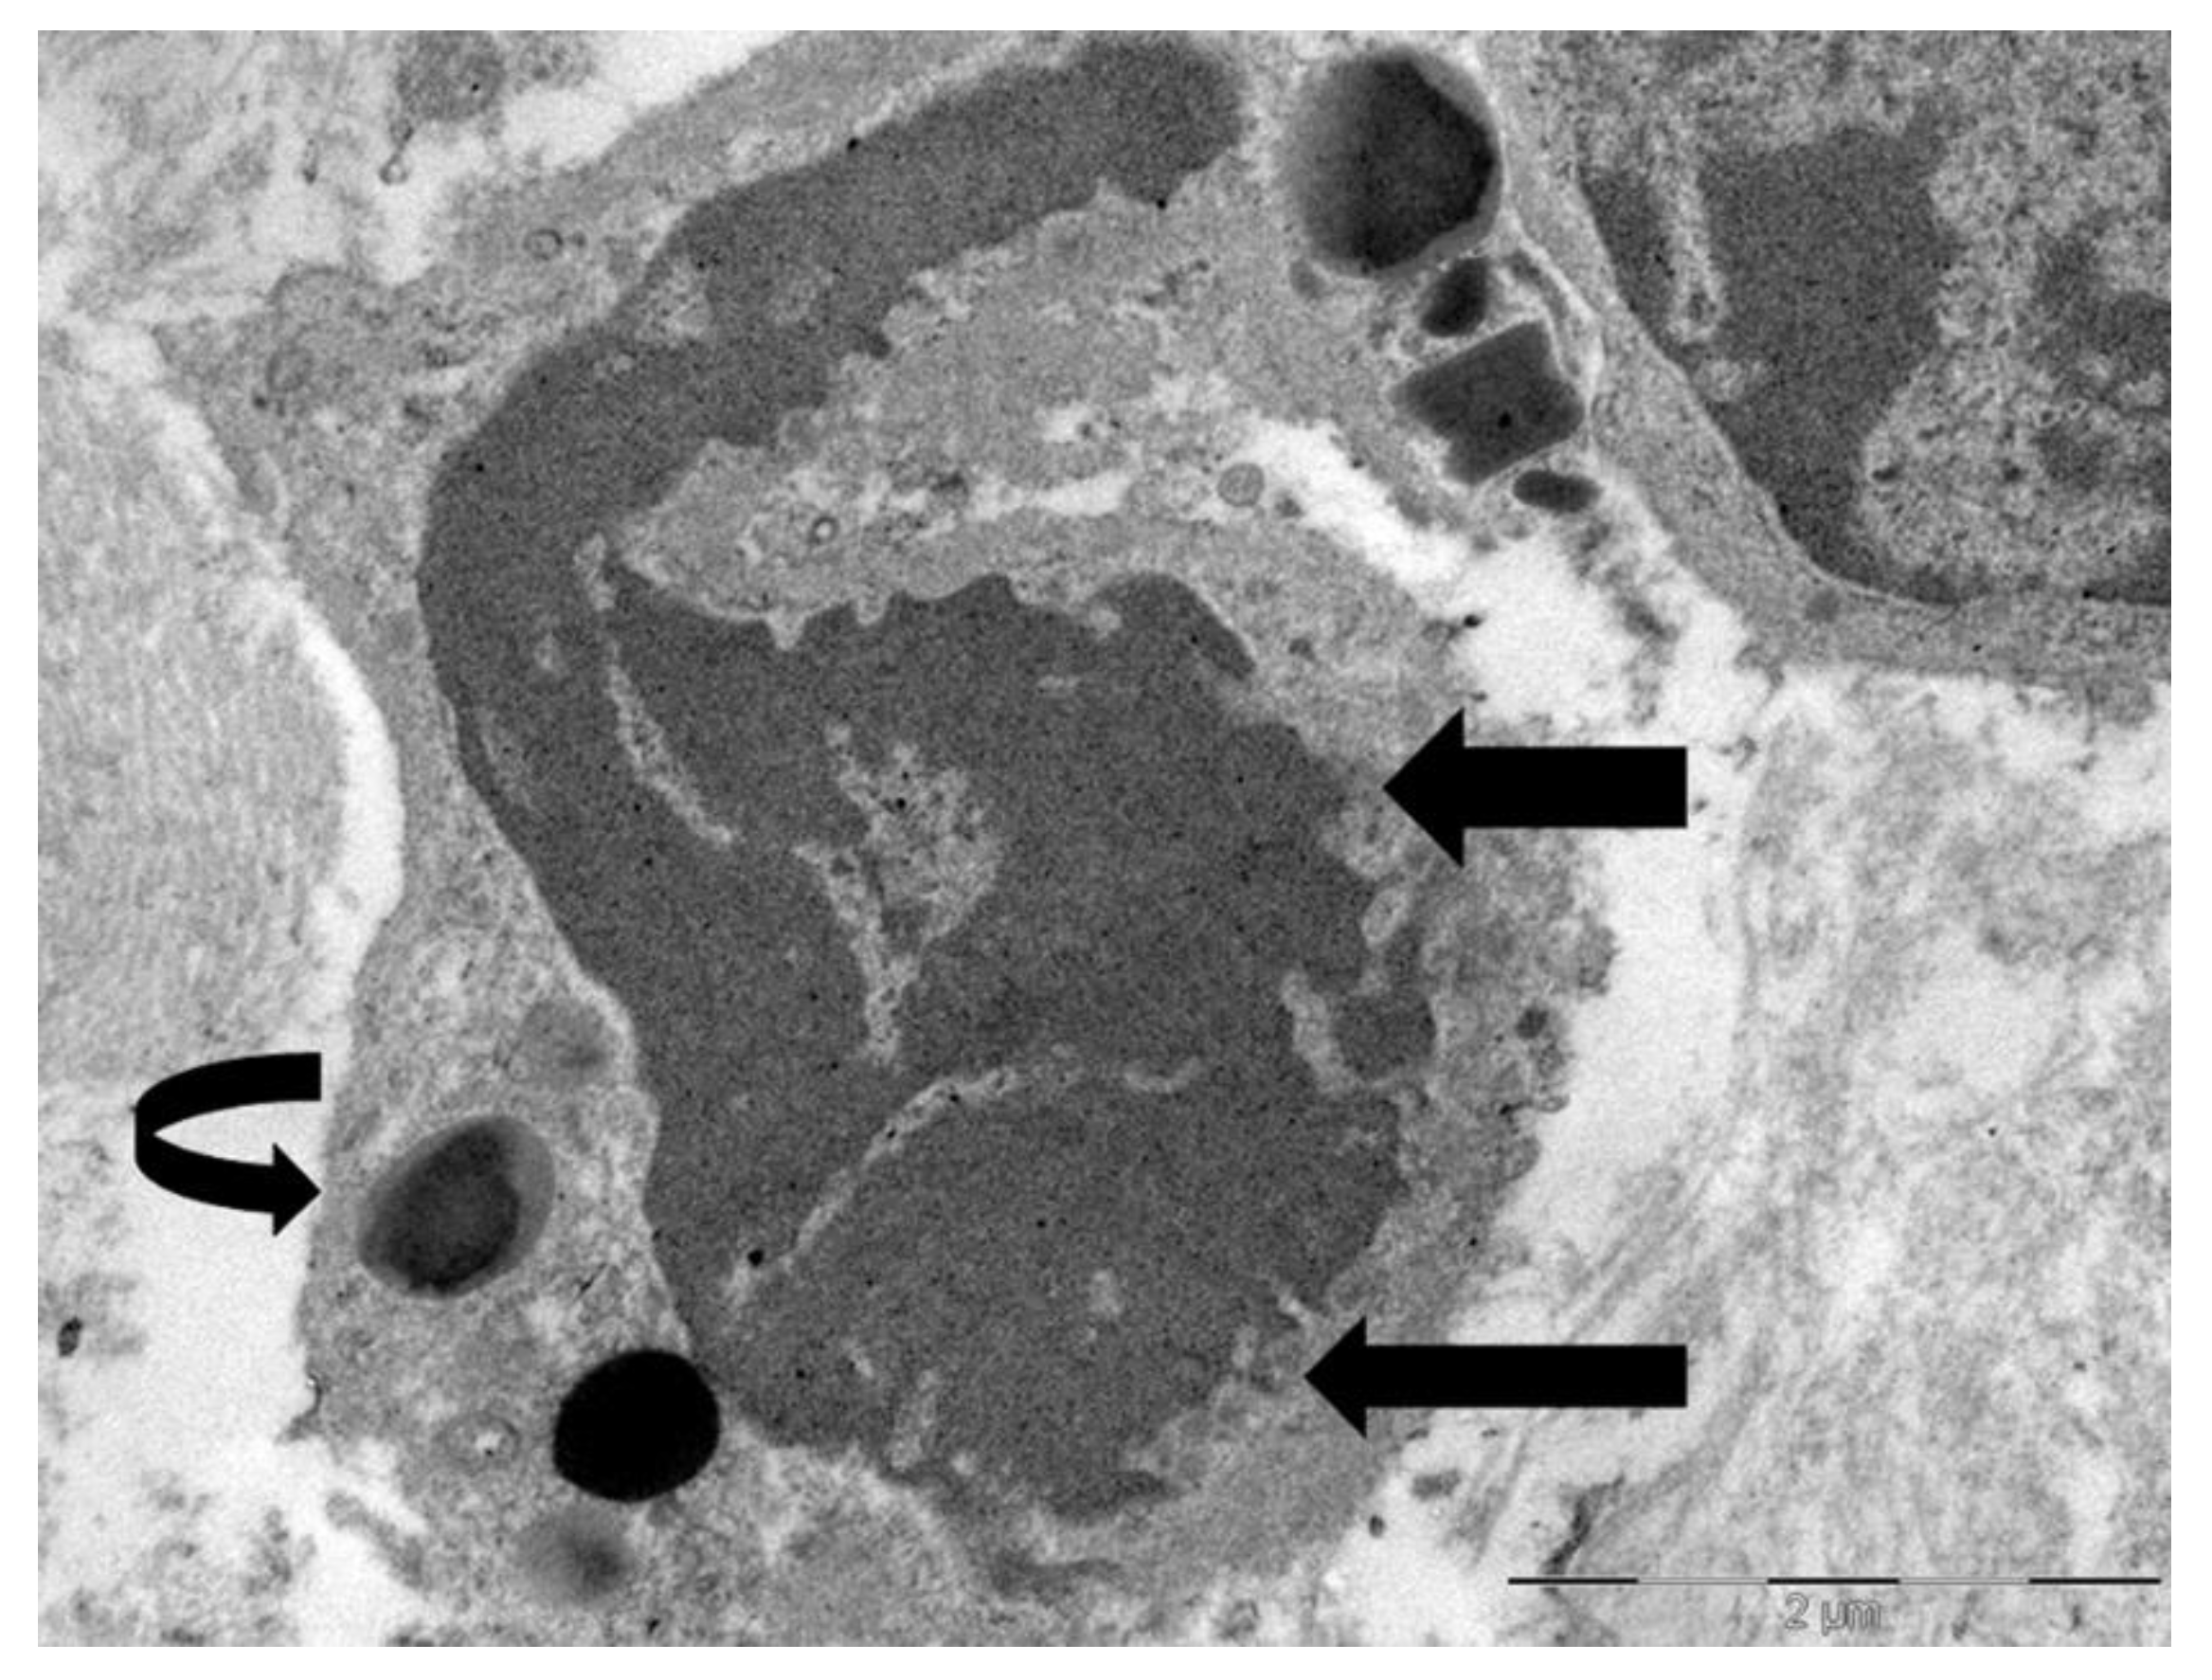

Neves et al. [15] showed that in non-neoplastic eosinophil-associated disorders, not all cytolytic eosinophils had characteristics of ETosis, suggesting that this process may be limited to a distinct subset of activated eosinophils. Our ultrastructural investigations in gastric malignancies with TATE [31] confirmed and extended the processes of eosinophil ETosis described in non-neoplastic eosinophil-associated disorders. In particular, in three cases of gastric cancers we observed cytolytic eosinophils without ETosis. These eosinophils exhibited focal plasma membrane disruption, with release of FEGs, that retain their biphasic structure- dense core and surrounding matrix - and are scattered among collagen fibers near tumor cells. The nucleus maintained its bilobed morphology, with incomplete heterochromatin decondensation, and the nuclear envelope appeared mostly preserved or only mildly dilated (Figure 1).

Figure 1. Electron micrograph of an eosinophil showing ultrastructural signs of cytolysis such as rounded nuclear lobes, chromatin decondensation and the release of FEGs (black arrows).